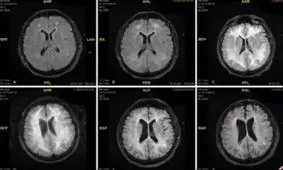

یک تیم پزشکی در بریتانیا تصاویری از اسکن مغزی یک بیمار را منتشر کردهاند که در اثر مصرف کوکائین دچار مشکلات جدی شده…